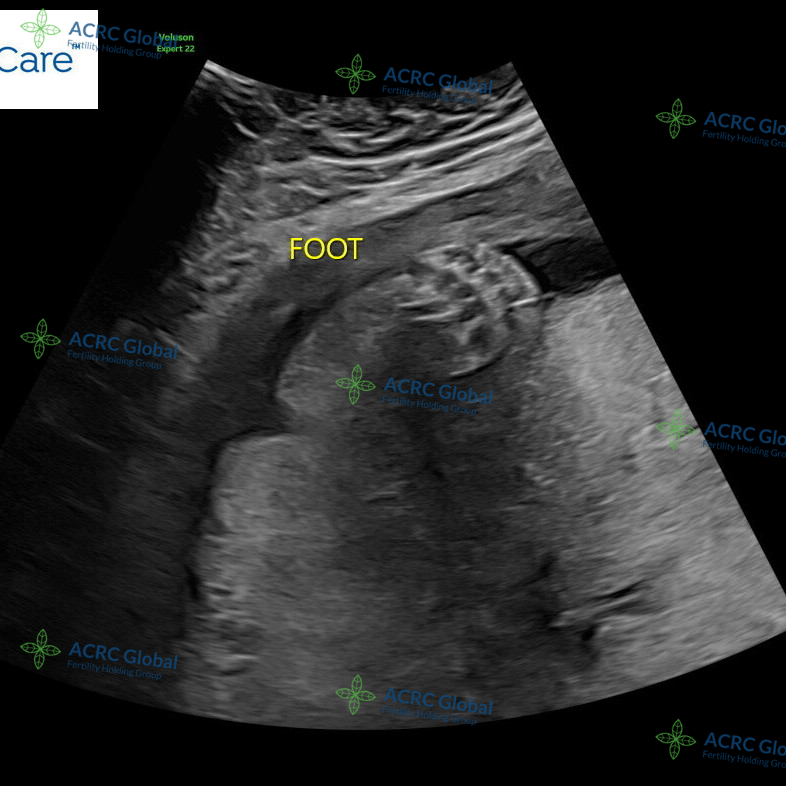

28周宝宝B超孕检

爱妈J已经进入孕28周,最近的B超检查显示,宝宝的发育一切良好。五官和四肢已经清晰可见,脸蛋的轮廓愈发可爱,甚至小脑袋上已经长出了柔软的头发。宝宝的手指和脚趾也在逐渐形成,整个模样越来越清晰,仿佛正在和外界悄悄打招呼。准父母看到这些健康的发育情况,心里感到无比踏实,他们已经迫不及待地期待与宝宝见面的那一天。

五官四肢清晰可见